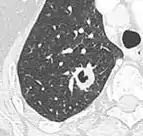

Round well-delineated solid lung nodule with smooth border.[9]